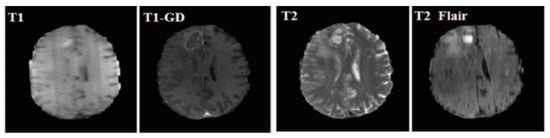

A brain tumor can be defined as a cancerous or noncancerous mass or development of abnormal cells in the brain. Gliomas can be categorized into High-Grade Glioma (HGG) and Low-Grade Glioma (LGG), based on the pathological assessment of the tumor. Brain tumor segmentation seeks to separate healthy tissue from tumorous regions. This is a crucial step in analysis and treatment planning to improve the possibility of effective treatment. Nowadays, biological science has emerged with several extended research problems under the category of Digital Image Processing (DIP). The detection of the tumor and its classification, detection of the cancerous region and its classification, testing, and inspecting crucial parts of the human body are some applications that fall under this category. Out of various medical science problems, automatic brain tumor segmentation and detection is of utmost importance, and efforts are being made in order to effectively handle this problem. A January 2020 Cancer.net editorial approved a report that estimated that this year, 23,890 adults, i.e., 13,590 males and 10,300 females, will be identified with cancerous tumors of the brain and spinal cord in the USA. In general, brain tumor diagnosis usually starts with Magnetic Resonance Imaging (MRI). The suspicious regions are separated using magnetic resonance segmentation using a complicated clinical imaging process. MRI is the most commonly used process that highlights the tumorous region in the brain, although brain tumor detection is still a manual process, examined and validated by experts. Thus, we require a compelling process to identify brain tumors in the early stage to save patients with high accuracy. There are some issues in the manual process, due to which the automatic detection of brain tumors becomes pivotal. Computer-aided detection of abnormal growth of tissue is primarily motivated by the necessity of reducing human error and thus achieving maximum possible accuracy. Using automated algorithms for the accurate and robust predictions of overall survival for patients diagnosed with gliomas can provide valuable guidance for diagnosis and necessary treatment. Furthermore, there is a lack of skilled Oncologists and Neurologists, especially in developing countries. According to a report in 2018, the country is facing a severe shortage of caregivers, with merely 2000 oncologists looking after around 10 million patients (https://timesofindia.indiatimes.com/india/India-has-just-2000-oncologists-for-10-million-patients/articleshow/50842842.cms). Owing to the presence of abnormalities, no conventional technique can be developed for the segmentation of brain tumors in the medical field. Generally, magnetic resonance image (MRI) scans are utilized for the proper examination and diagnosis of brain tumors. This study systematically works on the detection of brain tumors using MRI images []. Owing to the profound significance of machine learning and deep learning, a vast number of methods have been developed, mostly using a specific technique, i.e., machine learning or deep learning []. Despite initiating a breakthrough in handling tumor detection tasks, existing applied deep learning models have some drawbacks. CNN-based deep learning techniques require high volume data, which makes it a complex and expensive task. Massive features are necessary to train tumor detection and segmentation accurately. However, the U-net model of CNN has shown great help in prognosticating in medical image segmentation. In recent literature, numerous works are done either using variation in U-Net architecture or with some pre/post-filtering for outcome improvisation. A Multi-Inception-UNet architecture is proposed to improve scalability and is applied to BraTs 2015, 2017, and 2019 datasets []. This is considered the latest work done in this same direction with the help of this same U-Net Model. MRI Brain Tumor segmentation is validated using 3D-UNet on the BraTs’20 dataset, where the author achieved an accuracy of 0.83 on the training set and 0.82 on the validation set []. The proposed work is somewhat motivated by the work done by Jurdi et al. in June 2020; in their work, U-Net with Bounding Box Prior is applied to two public datasets—SegTHOR is Computed Tomography (CT) images and another Cardiac dataset is a mono-modal MRI dataset. A bounding box (BB) filter is inserted at the BBConV Layer, by which researchers can achieve approximately 98.32% average dice coefficient []. Henceforth, in this study, a systematic process is performed for the detection of brain tumors using MRI images. The experimentation uses U-Net to exhibit the knowledge of deep learning models for tumor image segmentation. The deep learning model is applied for MRI segmentation on the BraTS 2018 dataset (https://www.med.upenn.edu/sbia/brats2018/data.html), which contains four different MRI modalities—T1, T2, T1Gd, and FLAIR of each patient (see Figure 1).

Figure 1.

A sample set of T1, T1-GD, T2, and T2 Flair images (Source: BraTS 2018 Dataset).

Corresponding to each patient, the segmented tumor region and OT (ground truth of tumor segmentation) are stated. Although experiments are primarily carried out on the BraTS dataset, a list of datasets used to perform brain tumor detection tasks is also tabulated in Table 1 for the readers’ point of view.